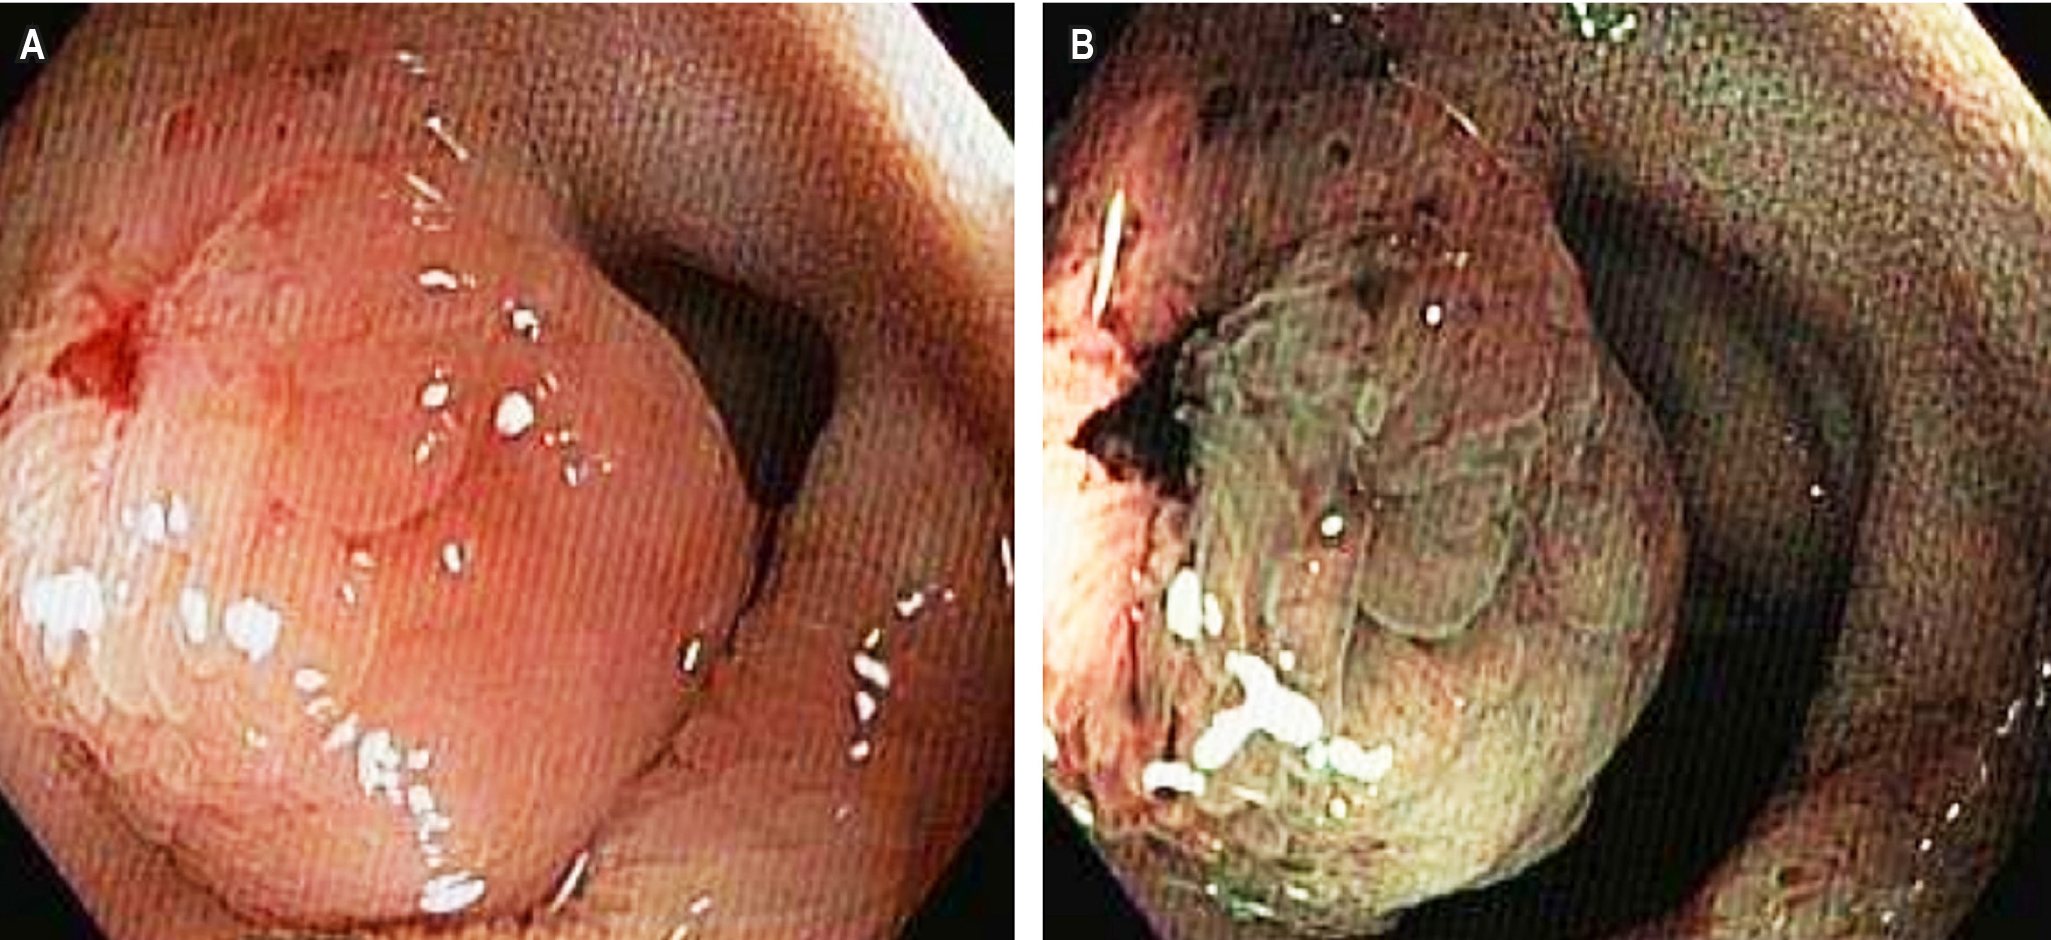

Case Presentation: We report the case of a 56-year-old female patient with a history of treatment-resistant hypertension since 2022. She was referred to gastroenterology due to diffuse, colicky abdominal pain, accompanied by bloating and two loose bowel movements per day for the past two years. A colonoscopy with ileal intubation revealed a 15 mm sessile polypoid lesion in the distal ileum, located 5 cm from the ileocecal valve. An octreotide scan identified an intraluminal lesion in the distal ileum with somatostatin receptor overexpression, as well as an enlarged right ileocolic lymph node. The patient underwent laparoscopic surgery, which included a right hemicolectomy, distal ileum resection, and retroperitoneal lymphadenectomy. The final histopathological diagnosis confirmed a grade 2 ileal neuroendocrine tumor measuring 1.5 x 1 cm, extending into the muscularis propria without lymphovascular or perineural invasion. Surgical margins were tumor-free. To date, the patient has not required adjuvant therapy during follow-up.